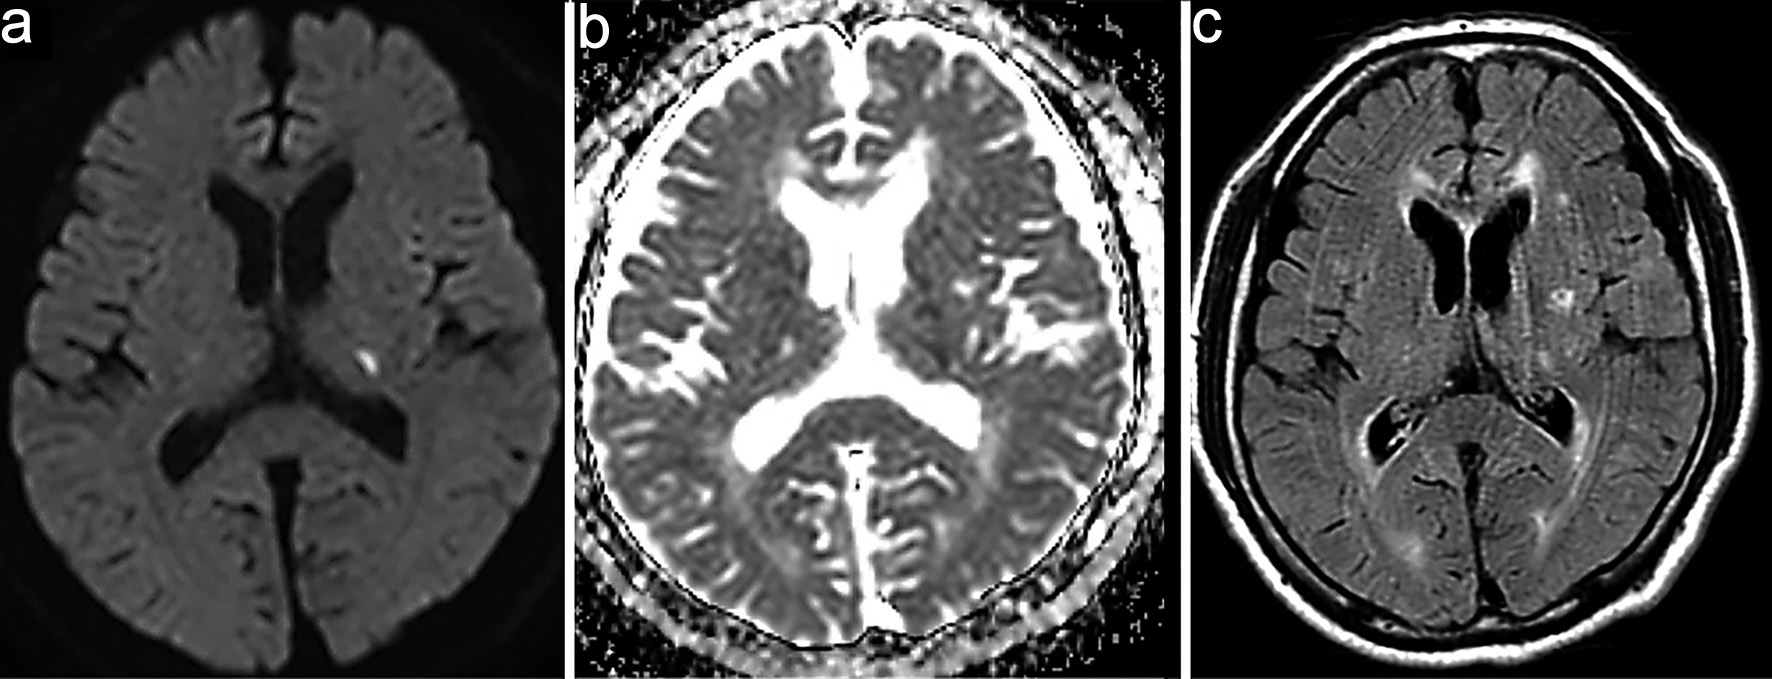

Click for large image

Figure 3. Contrast-enhanced magnetic resonance imaging (MRI) on day 11. (a–c) Contrast-enhanced MRI shows serpiginous perivascular enhancement in the basal ganglia along with leptomeningeal enhancement.